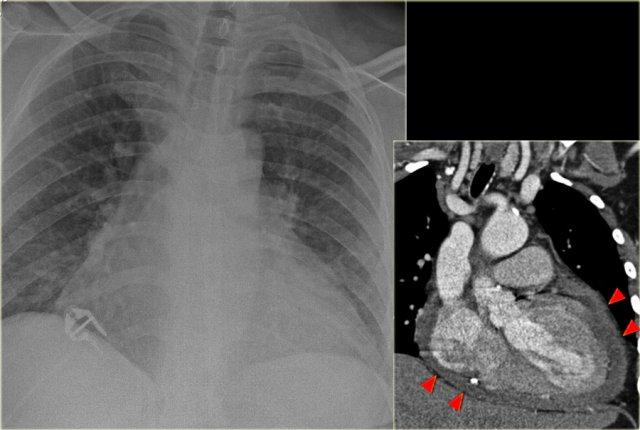

Hình bên trái là bệnh nhân vừa được phẫu thuật thay van tim.

Bóng tim lớn, có thể là hệ quả của tim to (cardiomegaly).

Do tiền sử phẫu thuật tim gần đây, khả năng tràn dịch màng ngoài tim đã được đặt ra và được minh họa rõ ràng trên hình ảnh CT.

Hình bên trái là một bệnh nhân khác có bóng tim lớn trên phim X-quang ngực do tràn dịch màng ngoài tim.

Tràn dịch màng ngoài tim được minh họa trên tái tạo CT mặt phẳng coronal.